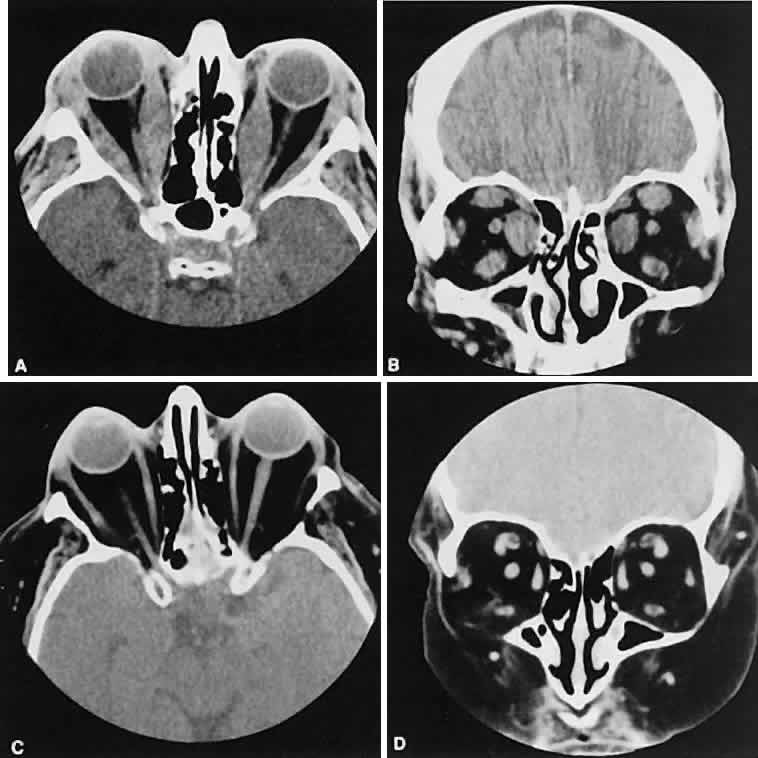

Optimal visualization of the orbit requires imaging from at least two planes. Axial slices should be oriented parallel to the optic nerve (-10 degreesto the orbitomeatal line) and no thicker than 3 mm. Axial views, because of volume averaging, may miss lesions located along the floor or roof. Additional views, typically coronal, can be obtained by reformatting data obtained during axial imaging or by direct coronal scanning.

Direct coronal views usually are preferable because of better resolution.6,7 They can be obtained by having patients lie either prone or supine, extending their neck, and angulating the gantry sufficiently to provide coronal imaging while avoiding artifacts from the teeth. Direct coronal scans also should be no thicker than 3 mm.

Coronal views may need to be reformatted from axial scans if a patient has extensive dental fillings, is anesthetized, or cannot extend the neck sufficiently for direct coronal scanning. The resolution on these images can be improved if data are collected from 1.5-mm contiguous axial slides.6 Spiral CT has resulted in improved multiplanar reformation with thin section (1 to 1.5 mm) axial images. High-resolution images necessary for leukocoria or foreign body imaging are obtained with 1-mm axial slices at 1:1 pitch at 1-mm intervals. Ideally, most screening orbit studies are performed at 3-mm direct axial and direct coronal images.

An appreciation for the various pathologic processes that affect the orbit is facilitated by an understanding of the normal orbital anatomy (Fig. 1). The orbit is a pyramid-shaped bony structure bounded inferiorly by the maxillary sinus, medially by the ethmoidal sinus, and superiorly by the frontal sinus. The sphenoidal sinus is situated posteriorly along the medial orbital wall and has a common wall with the optic canal. The lacrimal gland lies within its fossa located in the superior temporal aspect of the orbit and can be seen on both axial and coronal views.

The extraocular muscles (EOMs), with the exception of the inferior oblique, originate from the anulus of Zinn in the orbital apex. The inferior oblique takes its origin from the frontal process of the maxilla and is seen occasionally on CT imaging. The superior oblique, after originating from the anulus, courses along the superior nasal orbital wall just above the medial rectus muscle before passing through the trochlea. The rectus muscles conveniently form a muscle cone, which is sometimes helpful in terms of differential diagnosis. Before thinner axial slices and multiplanar imaging were available, an enlarged inferior rectus muscle often was imaged as an apical mass, especially if dysthy-roid optic neuropathy was present. The importance of imaging from two different planes cannot be overemphasized in this situation.

The superior ophthalmic vein (SOV) is an important vascular structure to recognize. It begins in the superior nasal quadrant near the trochlea before coursing posteriorly and laterally beneath the superior rectus muscle, exiting the orbit through the superior orbital fissure. Drainage is into the cavernous sinus. Asymmetric enlargement, especially in the presence of an ipsilateral cavernous sinus enlargement, suggests a vascular anomaly, which may require selective carotid angiography for further definition. Enlargement of one or multiple EOMs in this setting is likely. The SOV also may be enlarged as a result of any process impeding drainage from the orbital apex, such as dysthyroid orbitopathy or metastatic disease.

The optic nerve occupies the central intraconal space. By necessity, the nerve has a certain amount of slack, which is necessary to permit movement of the globe. In the axial plane, the optic nerve has an undulating course and thus may appear thicker or thinner as a result of partial volume averaging as it passes in and out of the axial plane. It is imperative to recognize this normal pattern for proper interpretation of axial images.